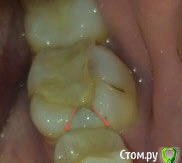

L_Z Опубликовано 19 апреля, 2015 Автор Поделиться Опубликовано 19 апреля, 2015 Фото для доп. информации. красным я отметила трещину. Ссылка на комментарий